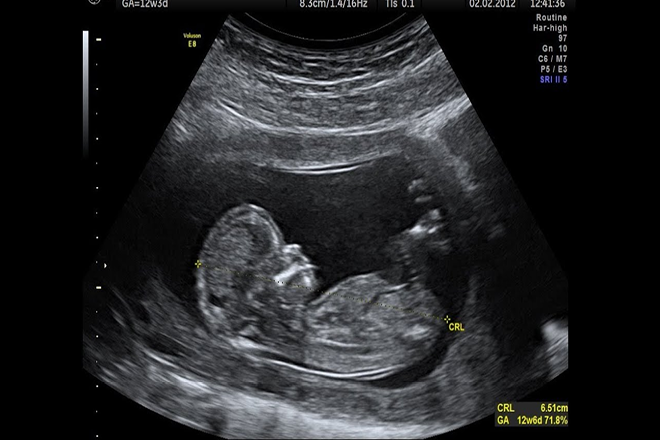

Una mujer policía embarazada fue asaltada por tres delincuentes que la abordaron cuando se dirigía a realizarse un control médico en la localidad bonaerense de Villa Tesei y se apoderaron de su cartera donde llevaba la ecografía de su bebé.

De inmediato, los ladrones se acercaron a la joven y a su pareja cuando cruzaban la calle para ir a realizarse un control médico y, si bien el hombre corrió y se alejó de los delincuentes, la mujer embrazada no pudo hacer lo mismo y fue atacada por los individuos que le robaron la cartera donde llevaba la ecografía de su bebé.